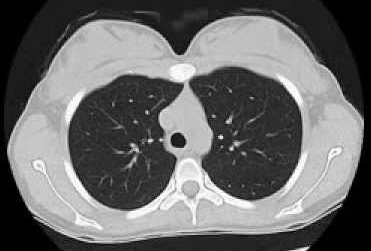

Run the model on a scan

Upload your own CT slice, or click any patient below to instantly see the model classify a real scan.

Try a real scan— click any patient to run inference instantly

OUTPUT

Select a patient above or upload your own scan to see results here.